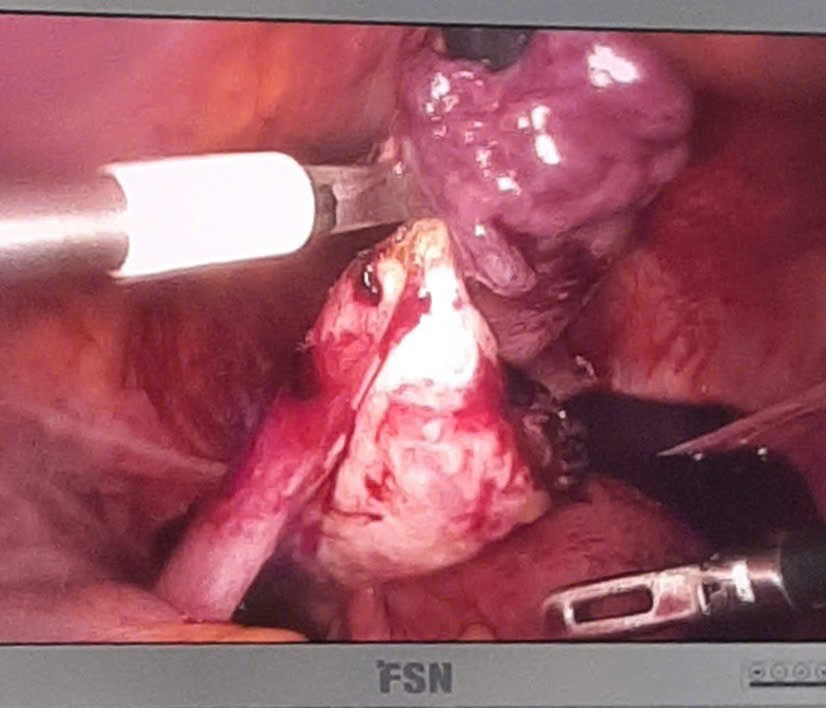

Phương pháp điều trị: phẫu thuật nội soi cắt khối thai ngoài

Hình 3. Khối thai ngoài tử cung vỡ và máu trong ổ bụng

Bệnh nhân được phẫu thuật ngay: